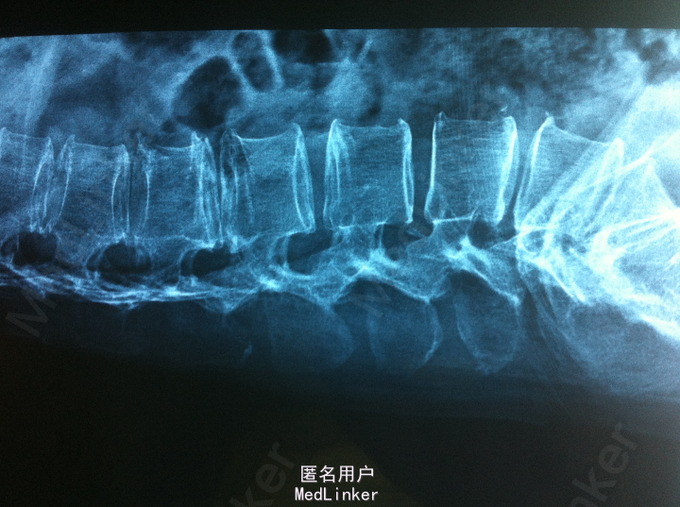

查体:腰部叩痛,腰部活动受限,左侧小腿外侧、足背感觉减退,左侧踝背伸、踇背伸、跖屈肌肌力4级,右侧踝背伸、踇背伸、跖屈肌肌力4-5级,双侧膝腱反射+,跟腱反射+,双侧巴氏征阴性。辅助检查: X-ray:腰椎退行性变节段性不稳。CT:腰椎间盘突出,腰3/4,4/5,腰5/骶1, MR:腰椎间盘突出,腰3/4,4/5,腰5、骶1椎间盘突出。